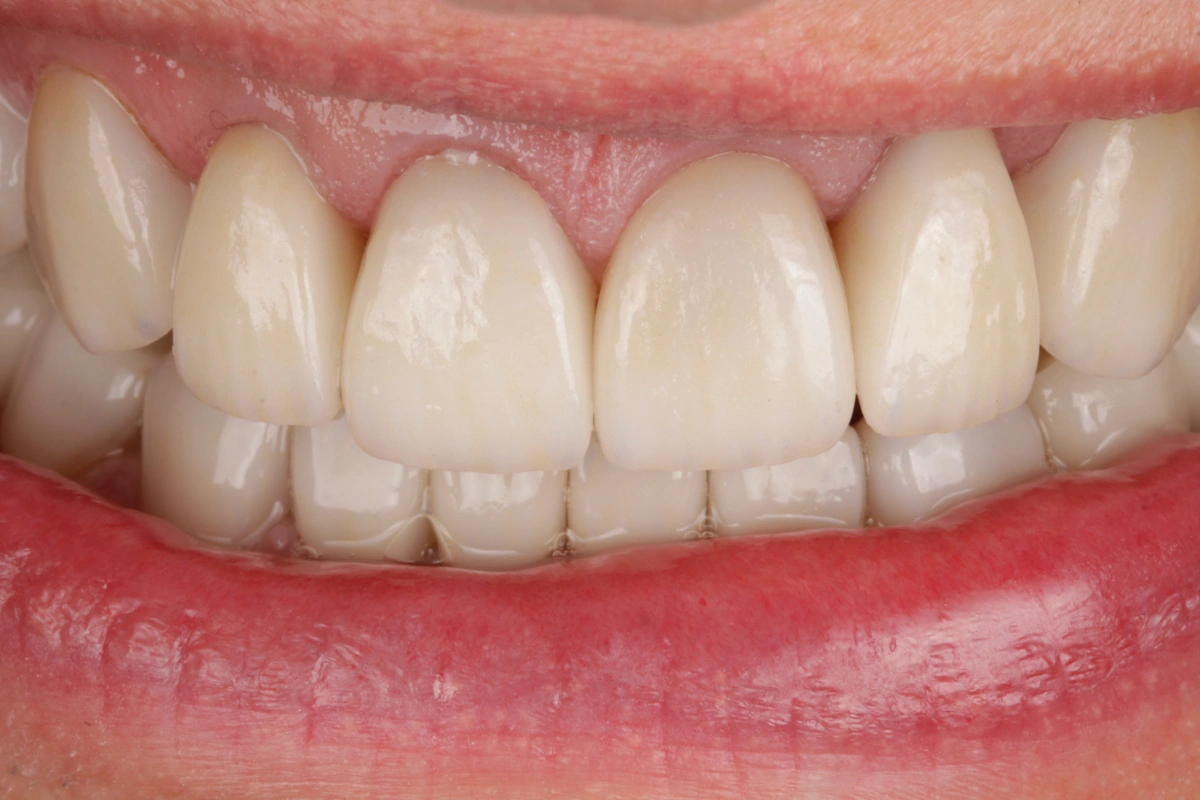

Tras realizar un estudio exhaustivo optamos por una rehabilitación completa con coronas, carillas e incrustaciones en disilicato de litio. Realizamos una prueba previa a la preparación de los dientes para establecer la longitud de los dientes definitivos.

Al finalizar el tratamiento, protegemos con una férula nocturna tipo Michigan.